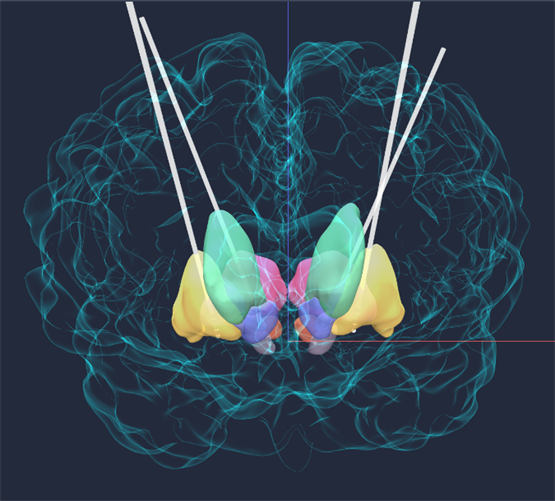

▲3D可视化模拟程控

“这相当于组建了一个‘大脑内部的交响乐团’,”郭铭主任用一个生动的比喻向家属解释,“GPi是管乐部,专治异动;STN和SNr是弦乐部,负责步态和僵直。‘一拖四’的设计,就是让这位指挥家(脉冲发生器)能同时协调四个声部,奏出和谐的生命乐章。”